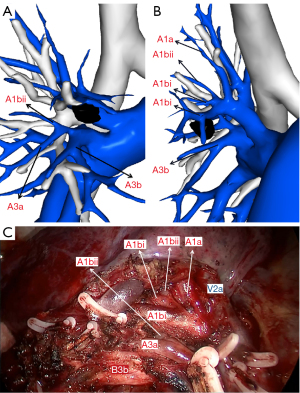

The pulmonary right upper lobe artery branching pattern of our case was superior trunk, inferior trunk, and an ascending artery. The superior trunk comprised A1 and A2a, while the inferior trunk comprised A3 and A1bii. We dissected 2 arteries, including A1bi and A3b. A1bi was located both anterior and posterior to B1bi, and A3b was located at the anterior side of B3b and shared a common trunk with A1bii and A3a (Figures 4,5).

The 3D reconstruction indicated the branching pattern of the pulmonary vein as an “anterior type”, V2a drained into the anterior V1 and V2t, and V2b, and V2c drained into the central vein. We planned to resect V1a and V1b to achieve sufficient surgical margins (Figures 4,6).